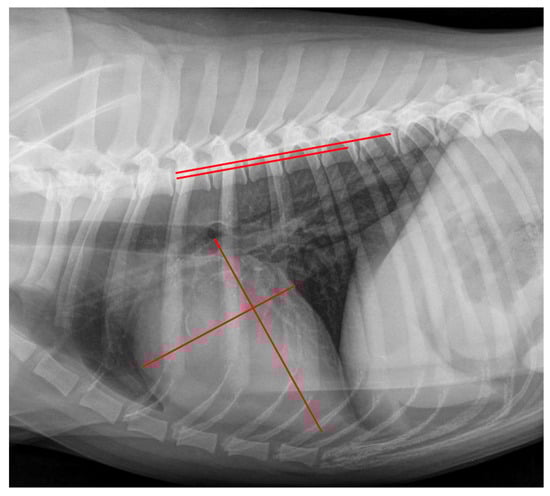

2.4. Radiographic Measurements